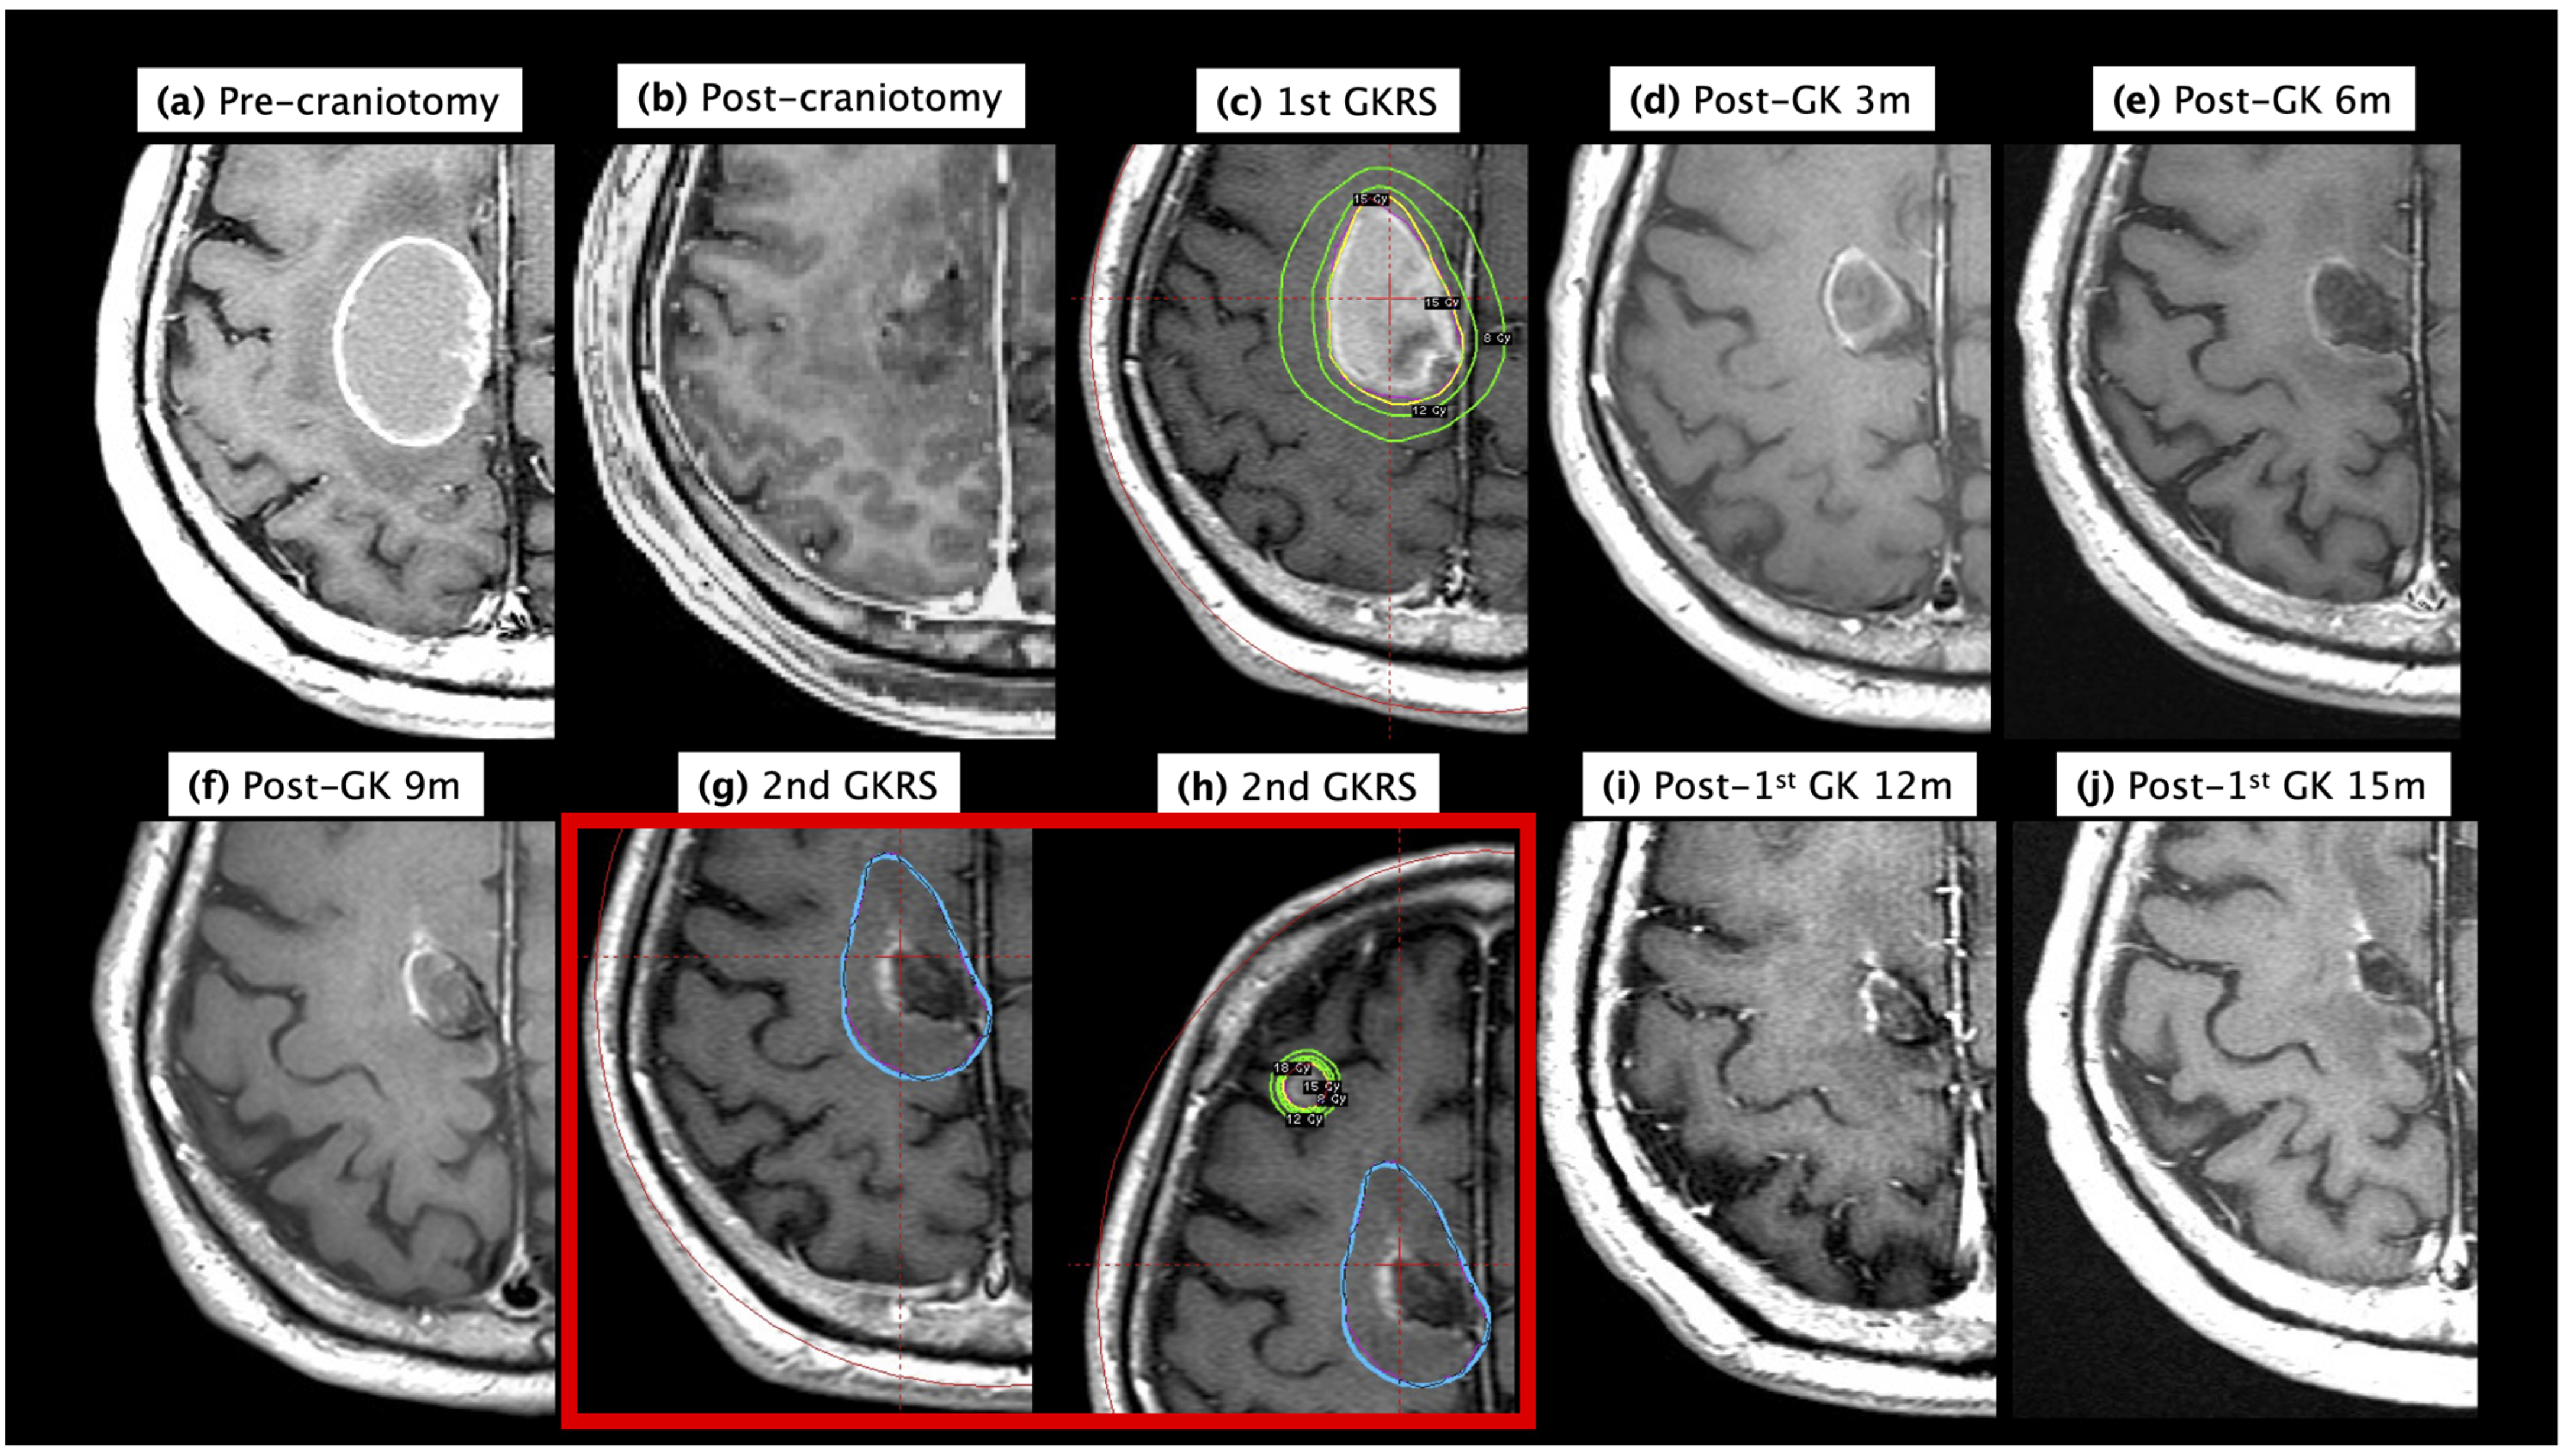

3.4. Demonstration Case